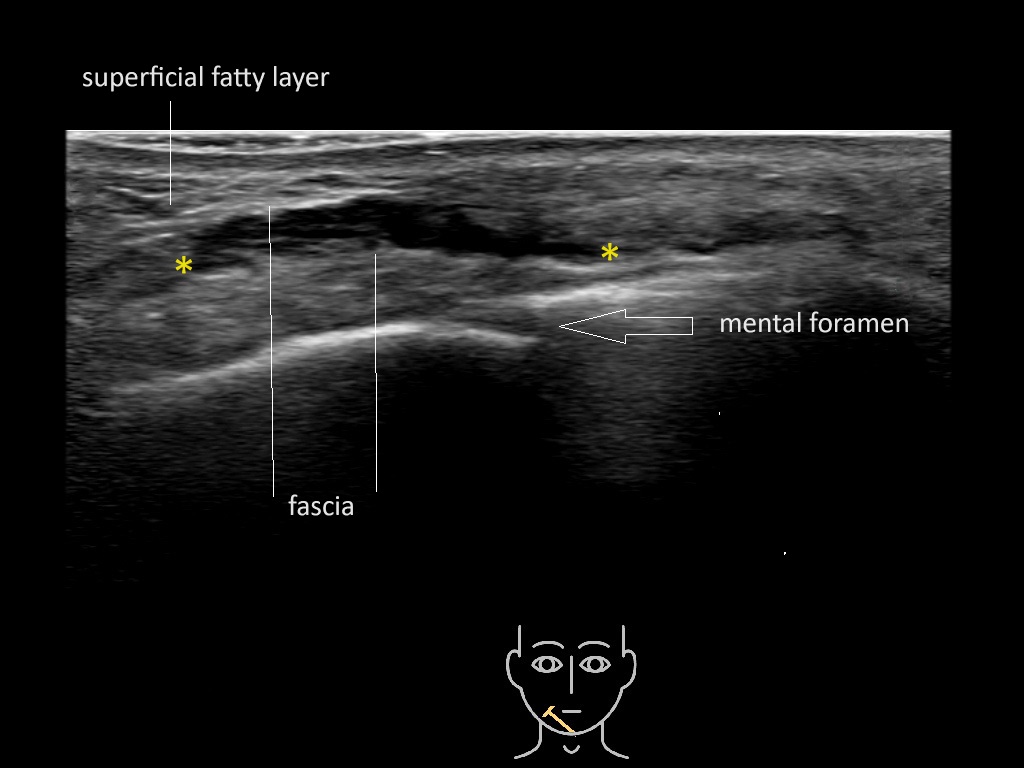

Filler deposits may end up unintentionally in the SMAS or fascial layers of the skin. Very often this will not lead to adverse events, however, adverse events ( nodules, migration / redistribution impaired muscle movement and smiling and malar edema) are are often related to filler ending up in the SMAS or fascia.

Study the first image to recognize the different layers. If you are sure about the layers, swipe to the second image to view the answer (if applicable).